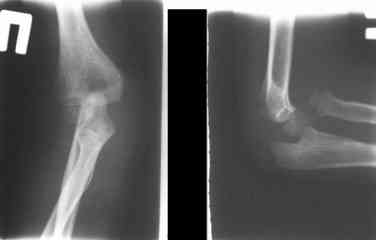

оперировали подобный случай около 6 мес назад. Отличие только в одном- давность травмы была до 2х лет. Использовали методику описанную в "Pediatric fractures and dislocations" Lutz von Laer, M.D.

Compact II выпущеный Stryker Howmedica, но за неименеем...), остеотомия проксимального отдела локтевой кости, вправление головки лучевой кости, замыкание аппарата, проверка стабильности головки

лучевой кости в движении, ушивание без пластики кольцевидной связки.

Данную методику применили впервые. После артролиза очевидная нестабильность головки луча. После остеотомии локтевой, вправления и

стабилизации аппарата головка луча при движениях на месте. Первые впечатления- "Либо чудо,либо фокус" (с) :))